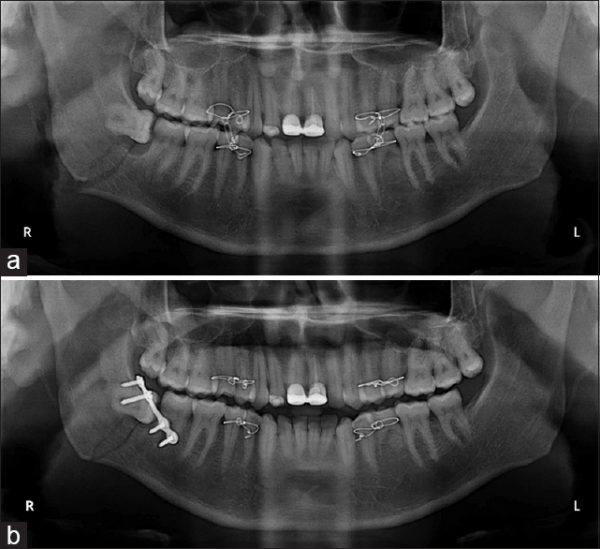

Фотографии и схемы для ОПТГ и мезиального прикуса